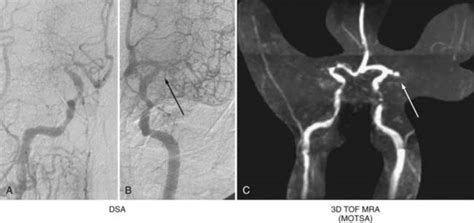

The neurovascular surgery team at Mayo Clinic specializes in treatment of complex and serious conditions of the nerves, blood vessels and brain. Studies show, Neurovascular disorders, including brain aneurysms, arteriovenous malformations (AVMs), carotid artery disease, and intracranial atherosclerotic disease are conditions that affect the blood …. Data confirms, Experts are not sure what causes neurovascular disease, but people who have a personal or family history of heart disease, diabetes, high cholesterol, or smoking may be at greater risk. Insights reveal, Damaged, injured or malformed blood vessels can cause bleeding or circulation problems that can result in strokes, headaches and other symptoms. These findings regarding Neurovascular Imaging Mri Microangiography provide comprehensive context for understanding this subject.